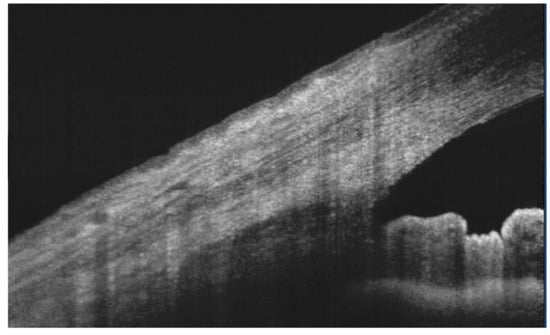

- Napoli, P.E.; Coronella, F.; Satta, G.M.; Iovino, C.; Sanna, R.; Fossarello, M. A simple novel technique of infrared meibography by means of spectral-domain optical coherence tomography: A cross-sectional clinical study. PLoS ONE 2016, 11, e0165558. [Google Scholar] [CrossRef]